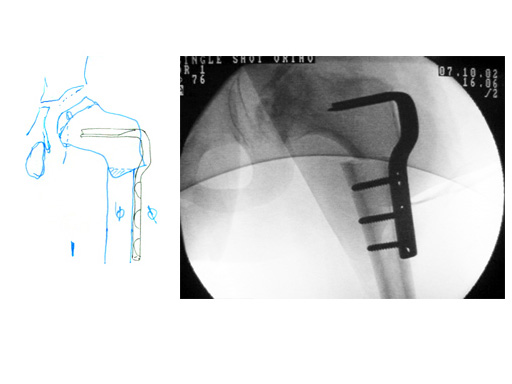

The 90 Toddler Osteotomy Plate 4 mm displacement with 38 mm blade length offers pediatric surgeons greater flexibility when performing intertrochanteric femoral osteotomies. The design of this Angled Blade Plate is identical to the existing 8 mm displacement with 38 mm blade length. The technique for insertion is the same.

Case 1:

6-year-old boy with Legg-Calv-Perthes disease.